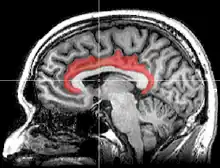

Sagittal MRI slice with highlighting indicating location of the cingulate cortex.

The cingulate cortex is a part of the brain situated in the medial aspect of the cerebral cortex. The cingulate cortex includes the entire cingulate gyrus, which lies immediately above the corpus callosum, and the continuation of this in the cingulate sulcus. The cingulate cortex is usually considered part of the limbic lobe.